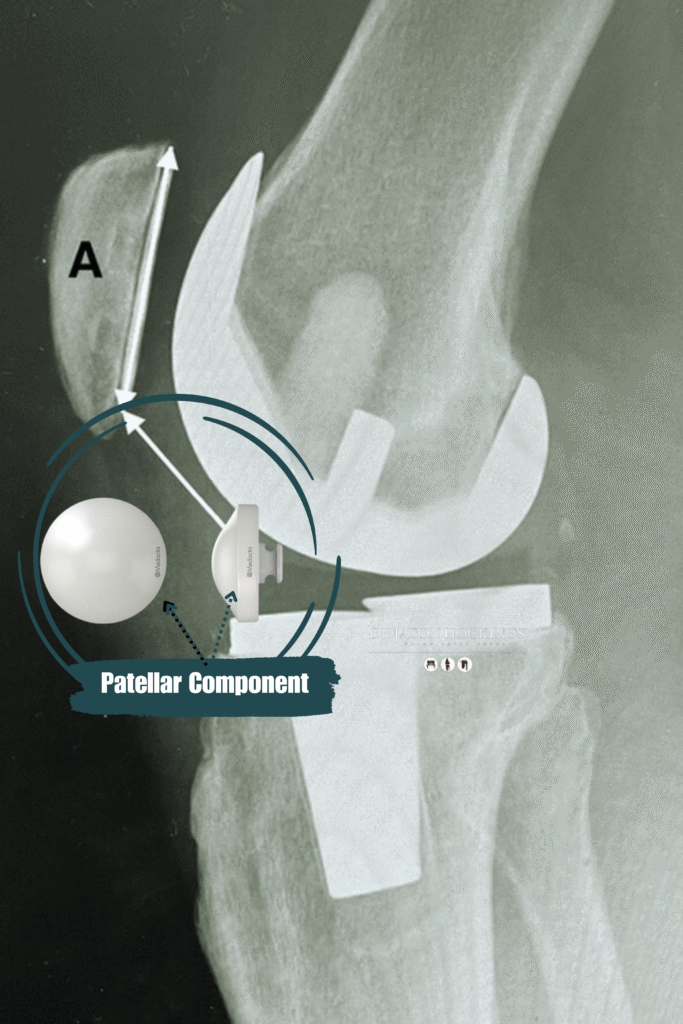

PATELLAR COMPONENT

(Optional)

A plastic button that may be attached to the underside of the kneecap (patella), depending on the degree of wear and the condition of your natural cartilage.

- Highly cross-linked polyethylene (plastic) for the tibial insert and patellar button, designed to reduce wear over time and improve joint longevity

- A patellar button may be added to resurface the back of your kneecap, depending on your condition